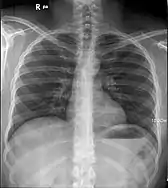

Les rayons X sont une des modalités principales de l'imagerie médicale[2] et du contrôle non destructif. Ils sont également utilisés en cristallographie. En astrophysique contemporaine, on mesure les rayonnements X de l'espace pour l'étudier.

Cent ans après leur découverte, on se sert encore des rayons X en radiographie moderne. On les utilise aussi dans les scanners, pour effectuer des coupes du corps humain, et dans les densitomètres pour détecter ou suivre l'ostéoporose. Plusieurs autres techniques sont actuellement utilisées en imagerie médicale : l'échographie (qui utilise les ultrasons), l'imagerie par résonance magnétique nucléaire, la scintigraphie ou encore la tomographie par émission de positons.

- ils pénètrent facilement la « matière molle », c'est-à-dire la matière solide peu dense et constituée d'éléments légers comme le carbone, l'oxygène et l'azote, et sont facilement absorbés par la « matière dure » (matière solide dense constituée d'éléments lourds) ; c'est ce qui permet l'imagerie médicale (radiographie, scanner, densitométrie osseuse) : ils traversent la chair et sont arrêtés par les os ;